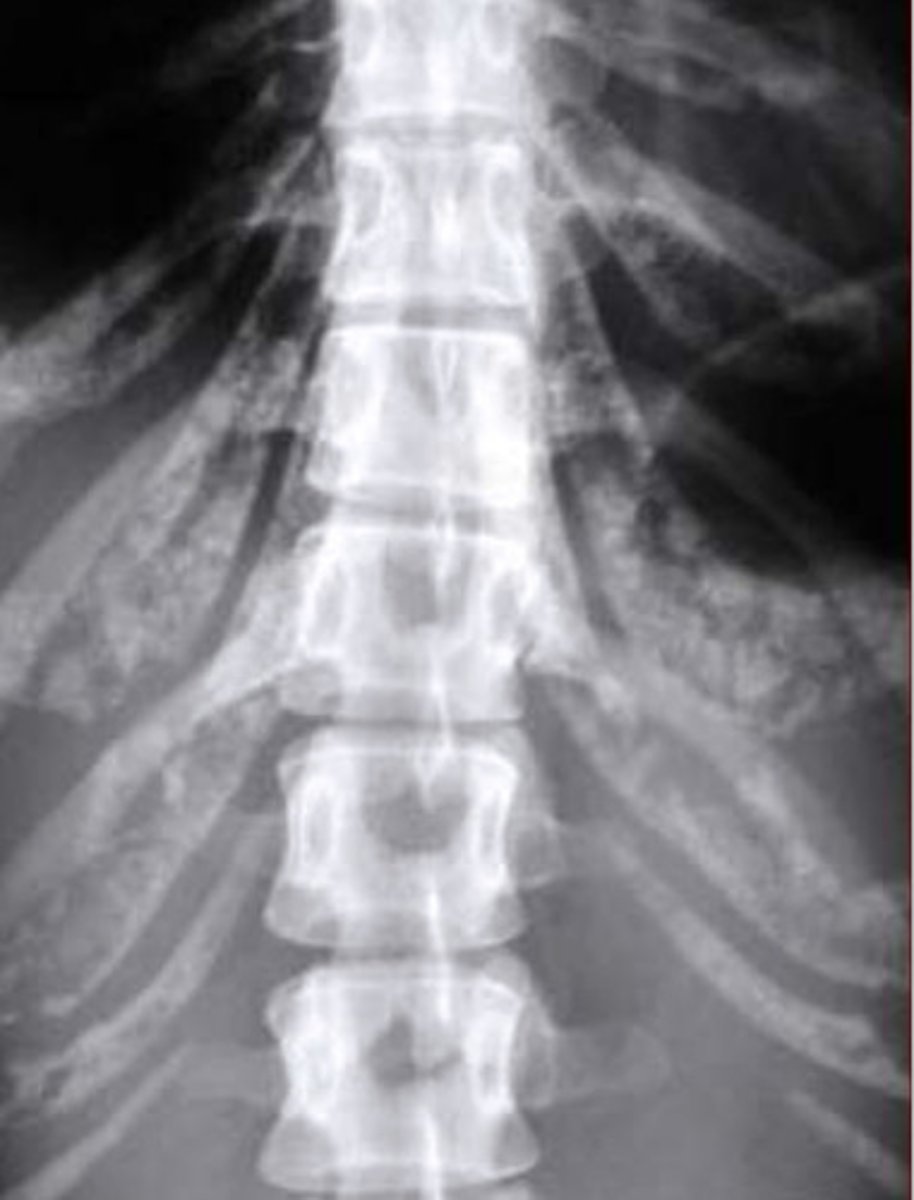

Sacralization = L5 doesn't fully segment from the sacrum (looks S1-like)

Lumbarization = S1 does not fully segment from L5 (looks L6-like)

Image example of sacralization of L5